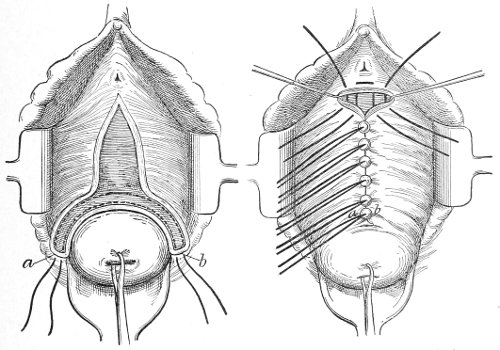

The secondary operation is performed at any time after cicatrization has occurred—often many years after the receipt of the injury. This operation is at present one of the commonest in gynecology, because the injury is not detected, is neglected, or is improperly repaired after labor. In the secondary operation an anesthetic is necessary. The mucous membrane must be removed or denuded on the posterior wall and about the mouth of the vagina, in order that the lacerated structures may be brought again in apposition. The denudation is best made by means of scissors curved on the flat (Figs. 24 and 25).

The strip of mucous membrane to be removed is picked up with a tenaculum (Fig. 26) or with tissue forceps 65 (Fig. 27); the scissors are placed with the blades parallel to the surface to be denuded, and the strip is cut away evenly, in one piece if possible. A similar contiguous strip is removed, and so on until the necessary surface is bare. Sponges in holders (Fig. 28) or continuous irrigation may be used to remove blood.

Slight Median laceration of the Perineum.—In this injury the tear takes place through the fourchette. Posteriorly it may extend as far as the sphincter ani muscle. Upward it may extend for an inch up the posterior vaginal wall. The appearance of this tear is shown in Fig. 33. It will be noted that, as this tear takes place in the median line, none of the muscles that support the perineum are involved, nor are the planes of fascia injured. The perineum is slightly split, and the insertions and origins of the muscles and the fascia are slightly separated. The supporting structures of the perineum and the pelvic floor are, however, uninjured.

Fig. 33.—Recent slight median laceration of the perineum: sutures introduced.

If this tear is detected after labor, it should be closed by the immediate operation. A slight tear involving chiefly the cutaneous aspect of the perineum should be closed by three or four sutures introduced from the outside, as in Fig. 33. The needle should be introduced about a quarter of an inch from the edge of the wound. It should not be passed parallel with the plane of the lacerated surface, but should be swept outward and then inward toward the 68 angle at the bottom of the tear (Fig. 34). It may either emerge at the angle and be re-introduced, or it may be passed directly through to the skin-margin on the opposite side of the wound. If the suture is passed in this way, there will be perfect apposition throughout the whole surface of laceration. If the sutures are improperly passed, there may result only apposition of the skin-edges.

Fig. 34.—Diagram representing the correct and the incorrect method of passing the suture for closure of slight perineal laceration.

If the laceration extends up the posterior vaginal wall, two sets of sutures must be introduced—one on the vaginal aspect of the tear, and one on the skin aspect (Fig. 35).